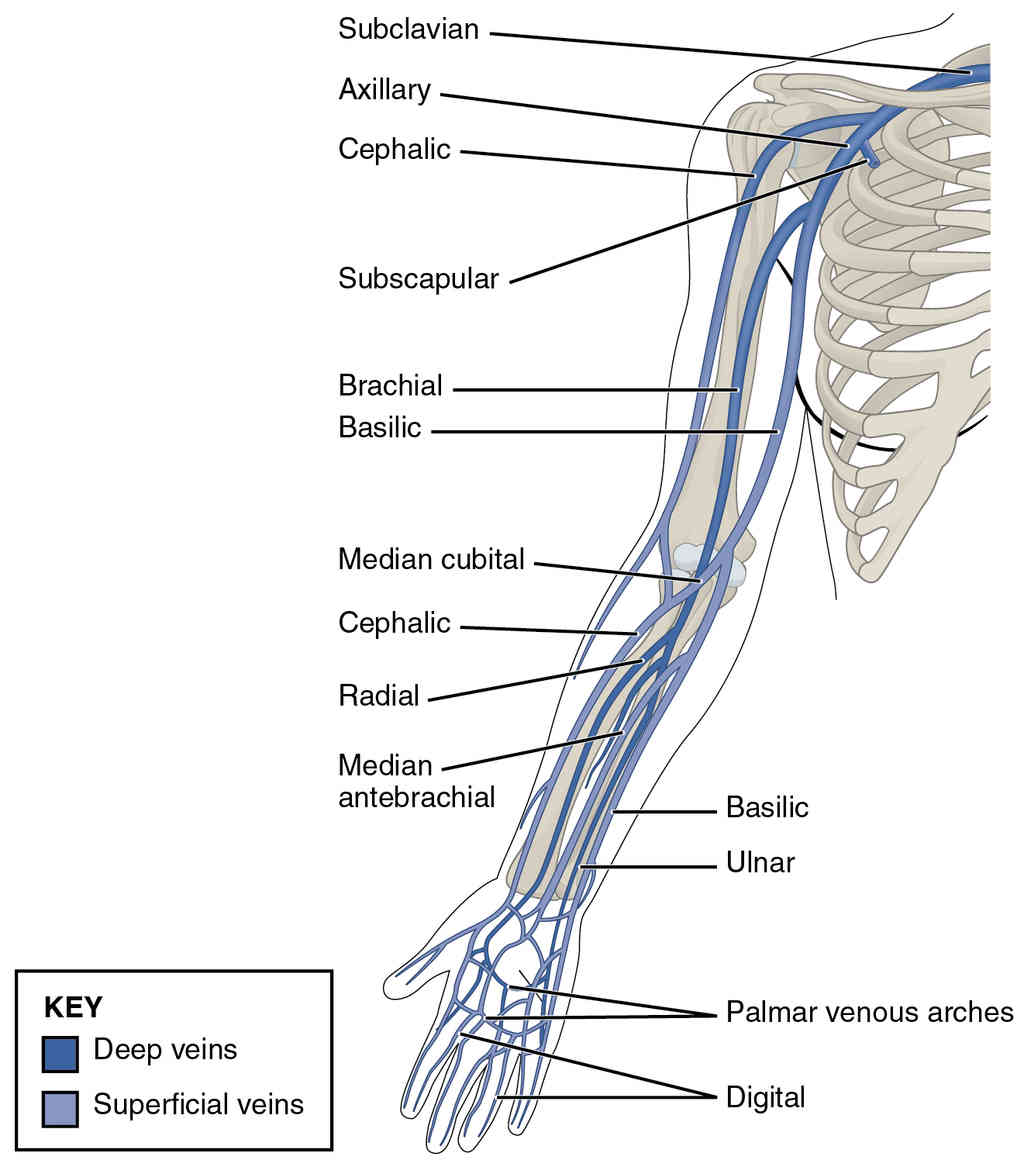

This page is under construction. For now, it is just a resource of the images found in the OpenStax Anatomy and Physiology Handbook. It wil slowly change into a revision tool. Each slide has a number. Use this to refer to the slide. When completed, it will have an unlabelled section, with labelled slides in parallel. On the unlabelled slides, write your answer and use the labelled slide to assess yourself. Keep track by also noting the number on each slide. Improvement at each attempt is important, more so than full marks on a first attempt.